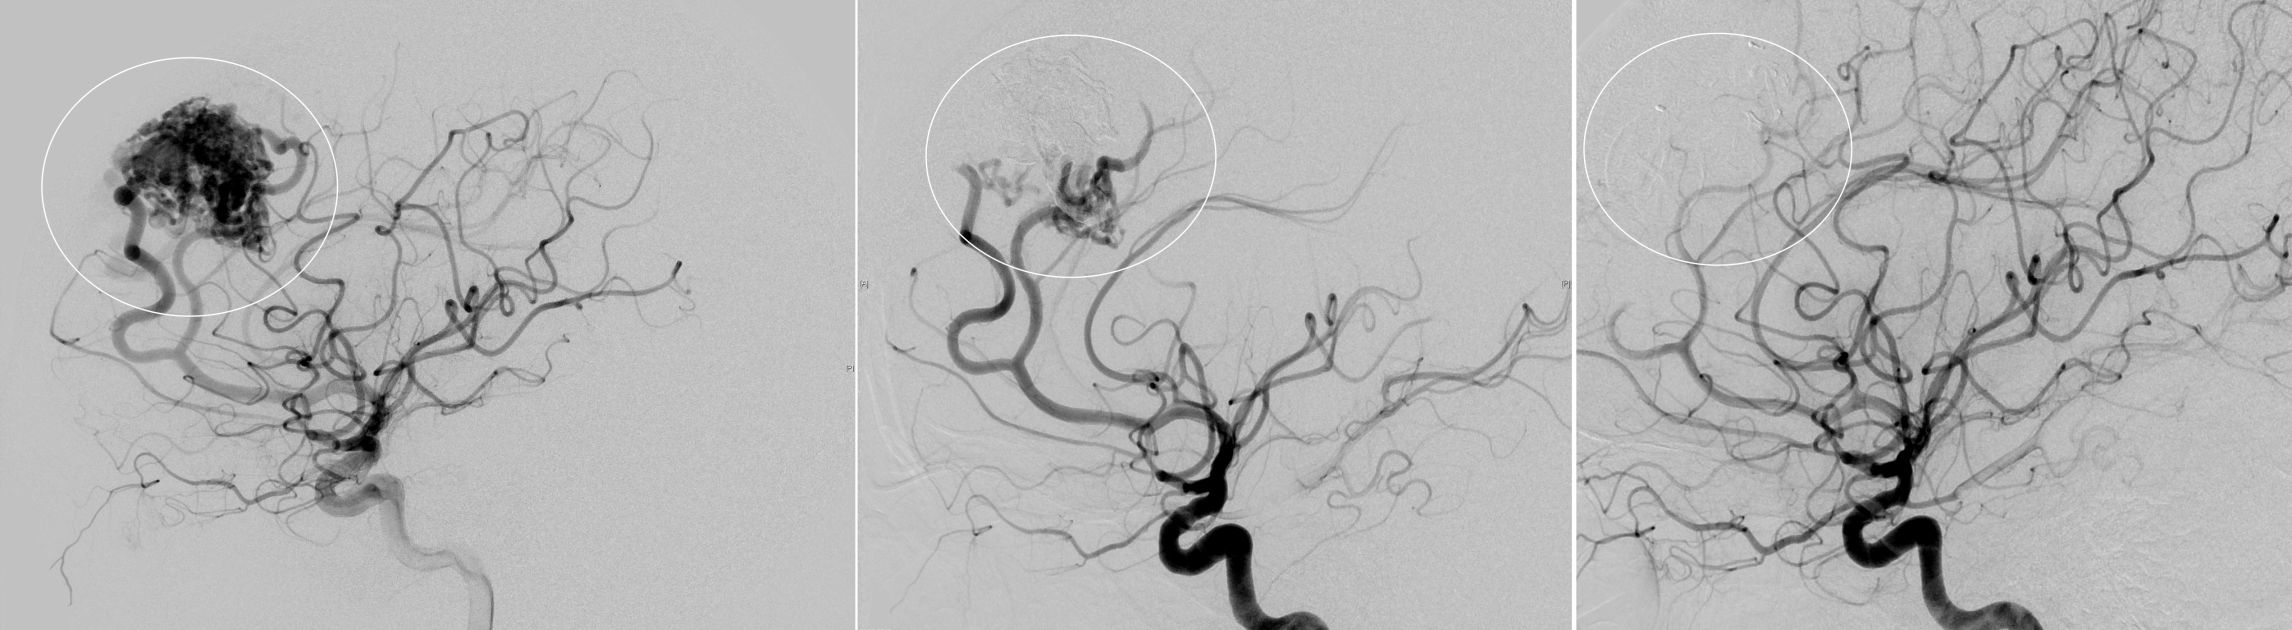

Angiographische Darstellung einer AVM

Angiographische Darstellung einer AVM vor dem Therapiebeginn (links), nach erfolgreicher Teilembolisation (Mitte) und nach vollständiger mikrochirurgischer Resektion (rechts)